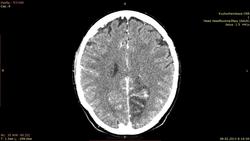

Пациент 67 лет. поступил с признаками онмк. на предыдуших томограммах гомогенное снижение плотности, по типу ишемии. через 10 дней улучшения нет. решили сделать с контрастом.Несколько дней назад у другого пациента с похожими симптомами нашли глиобластому. вот перестраховыаемся. подскажите это формирующаяся киста? как то не совсем нравятся участки контрастирования

Ишемический инсульт.

ишемический инфаркт в б.левой ЗМА. Дайком не качал, но по картинкам - самый обычный.

Опухоль должна иметь собственную ткань. А тут ее нет.

Ишемический инфаркт. Гиральный тип контрастного усиления; исчезает через 8-10 недель после развития заболевания.

Накопление по гиральному типу, ишемия в бассейне ЗМА.